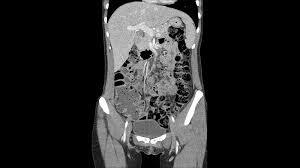

• Tomografia Axial Computarizada

Tomografia Axial Computarizada

Considerado uno de los 4 hitos o momentos trascendentes de la

Radiología. Fue un aporte del Físico inglés Sir Godfrey Houndsfield este nuevo descubrimiento nos permitió observar órganos nunca visualizados radiológicamente.